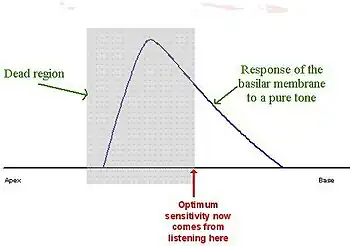

Cochlear dead regions in sensory hearing loss

Hearing impairment may be associated with damage to the hair cells in the cochlea. Sometimes there may be complete loss of function of inner hair cells (IHCs) over a certain region of the cochlea; this is called a "dead region". The region can be defined in terms of the range of characteristic frequencies (CFs) of the IHCs and/or neurons immediately adjacent to the dead region.

When the IHCs or part of the basilar membrane are damaged or destroyed, so that they no longer function as transducers, the result is a ‘dead region’. Dead regions can be defined in terms of the characteristic frequencies of the IHC, related to the specific place along the basilar membrane where the dead region occurs. Assuming that there has been no shift in the characteristic frequencies relating to certain regions of the basilar membrane, due to the damage of OHCs. This often occurs with IHC damage. Dead regions can also be defined by the anatomical place of the non-functioning IHC (such as an “apical dead region”), or by the characteristic frequencies of the IHC adjacent to the dead region.[15]

However, it appears that this is not the case. Dead regions cannot be clearly found via PTA audiograms. This may be because although the neurons innervating the dead region, cannot react to vibration at their characteristic frequency. If the basilar membrane vibration is large enough, neurons tuned to different characteristic frequencies such as those adjacent to the dead region, will be stimulated due to the spread of excitation. Therefore, a response from the patient at the test frequency will be obtained. This is referred to as “off-place listening”, and is also known as ‘off-frequency listening’. This will lead to a false threshold being found. Thus, it appears a person has better hearing than they actually do, resulting in a dead region being missed. Therefore, using PTA alone, it is impossible to identify the extent of a dead region (See Figure 7 and 8).[15]

Consequently, how much is an audiometric threshold affected by a tone with its frequency within a dead region? This depends on the location of the dead region. Thresholds at low frequency dead regions, are more inaccurate than those at higher frequency dead regions. This has been attributed to the fact that excitation due to vibration of the basilar membrane spreads upwards from the apical regions of the basilar membrane, more than excitation spreads downwards from higher frequency basal regions of the cochlea. This pattern of the spread of excitation is similar to the ‘upward spread of masking’ phenomenon. If the tone is sufficiently loud to produce enough excitation at the normally functioning area of the cochlea, so that it is above that areas threshold. The tone will be detected, due to off-frequency listening which results in a misleading threshold.[15]